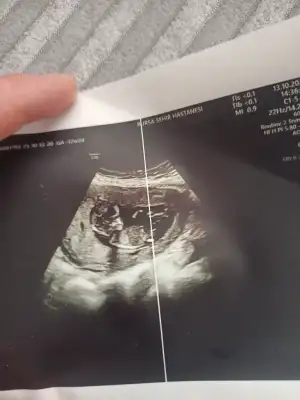

Banada yorum yapar mısınız

Banada bakar mısınız 12 haftalık 😊